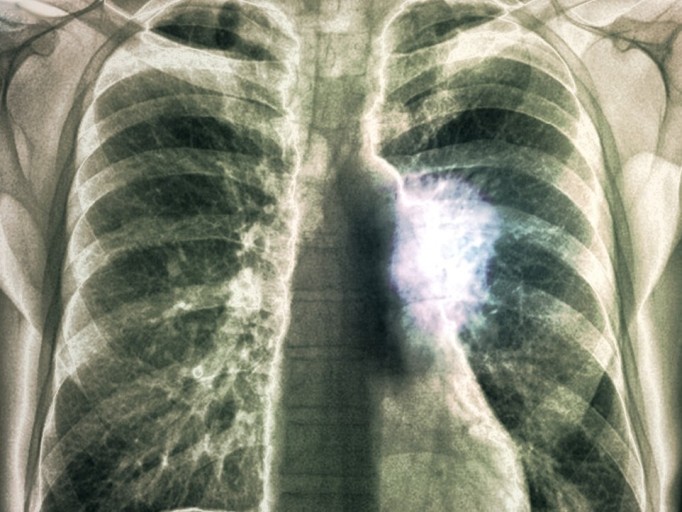

10. 피가 섞인 가래

폐렴이 심각하게 진행되면 가래에 피가 섞여 나올 수 있습니다. 이는 폐 조직이 손상되거나 염증으로 인해 혈관이 파열되어 발생할 수 있으며, 빨리 병원을 찾아 진료를 받는 것이 중요합니다.